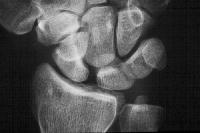

Preop

Click for larger image

Postop.